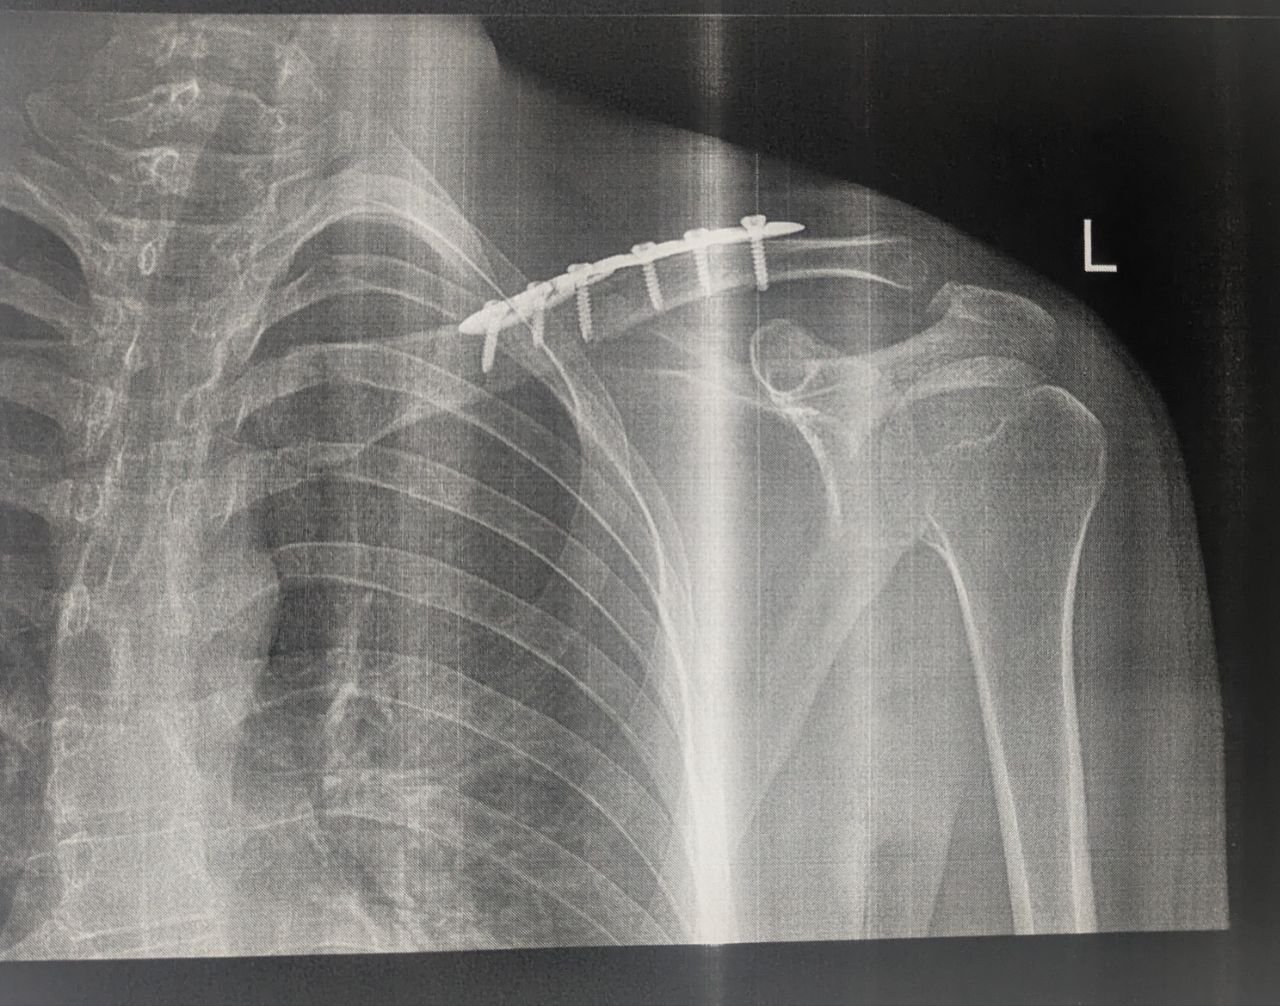

Хочу висловити щиру вдячність Досяку Мирославу Ігоровичу — лікарю з великої літери та справжньому професіоналу своєї справи.

Моя мама потрапила до нього зі складним випадком — перелом в області плеча. Ситуація вимагала високої точності, досвіду та швидких рішень. Операція пройшла швидко та успішно.

Особливо цінною стала його людяність. Мирослав Ігорович уважно ставився до мами, детально пояснював кожен крок, створював відчуття спокою та впевненості. Для мене, як для доньки, це мало величезне значення — я відчувала підтримку та залученість лікаря на кожному етапі.